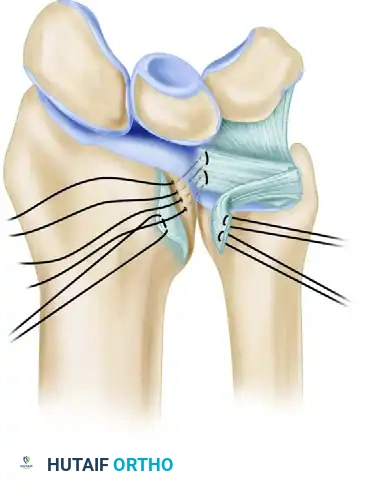

5. Transosseous Drill Holes and Suture Passage

- Utilize a 1.2-mm Kirschner wire (or a drill bit of equivalent size) to create a line of four side-by-side drill holes through the distal radius.

- The trajectory of these holes must be precise: drill from the dorsal surface of the distal radius (dorsoradial) directing the wire palmar-ulnar, ensuring the drill point exits exactly at the distal margin of the sigmoid notch, at the ulnar (medial) border of the lunate fossa.

- Select a high-tensile, absorbable suture—typically 2-0 or 3-0 polyglactin 910 (Vicryl) or polydioxanone (PDS)—armed with a small, round needle.

- Place horizontal mattress sutures into the substance of the avulsed TFCC. Pass the suture from the proximal undersurface to the distal surface of the fibrocartilage to ensure a secure bite.

Figure B: Suture placement into the TFCC through holes drilled in the dorsoulnar aspect of the distal radius. Horizontal mattress sutures are directed in a palmar and ulnar direction to exit at the edge of the lunate fossa and sigmoid notch.

- Remove the small needles from the sutures.

- To retrieve the sutures through the transosseous tunnels, pass a straight needle (without suture) in reverse through the drill holes to capture and pull the ends of the suture pairs dorsally. Alternatively, a wire loop (Hewson suture passer) or a specialized nitinol suture passer can be utilized with excellent efficacy.

6. DRUJ Reduction and Fixation

- Flex the patient's elbow to 90 degrees and position the forearm in neutral to slight supination. This position anatomically reduces the DRUJ and relaxes the dorsal radioulnar ligament.

- While maintaining this reduction, stabilize the DRUJ by driving a transarticular Kirschner wire (0.045-inch, 0.062-inch, or 2.0-mm) from the distal ulna into the radius, positioned just proximal to the sigmoid notch.

- With the joint pinned and reduced, systematically tighten the repair sutures. Tie the knots securely over the dorsal cortical bridge of the distal radius, just proximal to the lunate fossa.